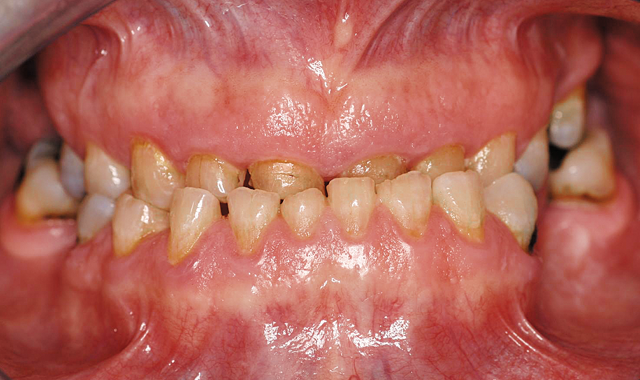

The patient's original smile.

01 The doctor was presented with a patient who had a multitude of oral issues, including a collapsed bite, an underbite and several rotting teeth. The goal was to create an esthetically pleasing six-unit anterior bridge that would drastically change the patient’s appearance and lifestyle (Fig. 1).